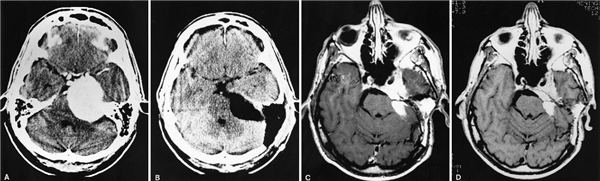

病例2:57岁女性,磁共振(MR)成像和计算机断层扫描(CT)显示一名患有步态共济失调和头痛的脑膜瘤粘连。A:术前检查发现轻度耳聋和步调不稳。通过显微外科手术方法切除大的右岩斜区肿瘤,在手术中,注意到内侧肿瘤密集地附着于脑干,决定实施次全切。术后即刻CT扫描(B)和2年后的随访MR研究(C)的比较表明没有进展的证据。

(注:以上病例来自世界神经外科学院主席William T. Couldwell教授论文山《岩斜区脑膜瘤:手术经验109例》)